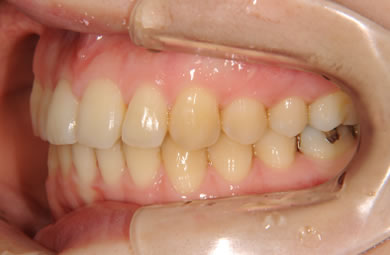

| 性別/年齢 | 女性 / 24歳 | ||||||||||||||||||||||||||||||||

| 治療方針 | 舌が横にはみでて、上下の歯が全く咬んでいない状態です。口元はきれいなので、歯は抜かずに歯列を少し横に広げて並べます。ゴムを使用したり、舌を訓練したりとても協力が必要な症例です。 | ||||||||||||||||||||||||||||||||

| 治療内容 | 唇側矯正(ホワイト)、保定装置 | ||||||||||||||||||||||||||||||||

| 治療期間 | 9ヶ月 |